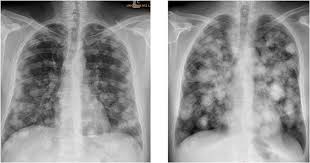

If the cancer has spread to the lungs sometimes testicular cancer spreads to the lungs. Testicular cancer begins in your testes, the male reproductive organ. When cancer originates in one or both testes, a man can go a long time without any obvious signs or symptoms. Stage iii testicular cancer has three subcategories: Most testicular cancer patients are between the ages of 20. Nce testicular cancer develops, it can remain within the testicle, or it can spread to lymph nodes in the abdomen or pelvis. So when testicular cancer spreads to the lung (or any other place), it's still called testicular cancer. Shortness of breath, chest pain, or a cough (even coughing up blood) may develop from cancer spread in the lungs. If cancer cells have spread to your lymph nodes (or beyond your lymph nodes to another part of the body), symptoms may include: Testicular cancer is highly treatable, even when cancer has spread beyond the testicle. If testicular cancer has spread to other parts of your body, you may also experience other symptoms. Certain types of testicular cancer are more likely to spread than others. Shortness of breath, chronic cough or chest pain can turn out to be the symptoms of testicular cancer that have affected the lungs.

If it is not detected and treated, testicular cancer eventually can spread to the lungs, brain, liver, and other parts of the body. It can happen, but the plumbing is such that if someone thinks they might have cancer, just see a doctor and find out for sure. More advanced stages may have spread to the liver and bones. And you might have one tumor in one lung or many tumors in both lungs. If found early, a testicular tumor may be about the size of a pea or a marble, but it can grow much larger.

Testicular Cancer Survival Rates Iranian Surgery from iraniansurgery.com If it is not detected and treated, testicular cancer eventually can spread to the lungs, brain, liver, and other parts of the body. When testicular cancer spreads, it most commonly spreads to the lung and the lymph nodes of the chest, pelvis, and the base of the neck. In stage 3 of the disease, the cancer has invaded other organs such as the lungs, brain or liver. It's not called lung cancer unless it starts from cells in the lung. It may have spread to the lungs or lymph nodes, but has not spread to anywhere else in your body. A painless lump or swelling on either testicle. There is no poor prognosis grouping for seminoma testicular cancer. Testicular cancer can usually be cured, even if it has spread when it is diagnosed.'

Lump or swelling in your neck, under your arm, or in your groin. It rarely spreads to other organs in the body. When testicular cancer spreads, it most commonly spreads to the lung and the lymph nodes of the chest, pelvis, and the base of the neck. Additional areas where testicular cancer may metastasize include the: Around 5% of people with testicular cancer will experience symptoms of metastatic cancer.